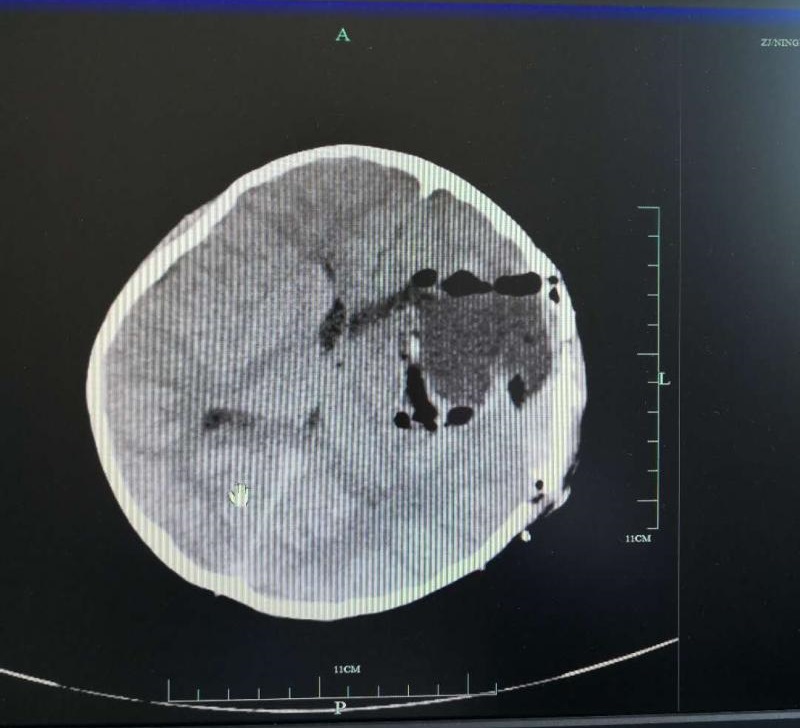

一周前,家住鄞州区的9岁小男孩李小宝(化名)突然出现头痛伴恶心、呕吐,被家人送往鄞州人民医院救治,经检查后确诊脑子里长了个瘤。该院神经外科专家高峰为其行完大脑半球病损切除术后转入ICU监护,现已脱离生命危险。

术后影像